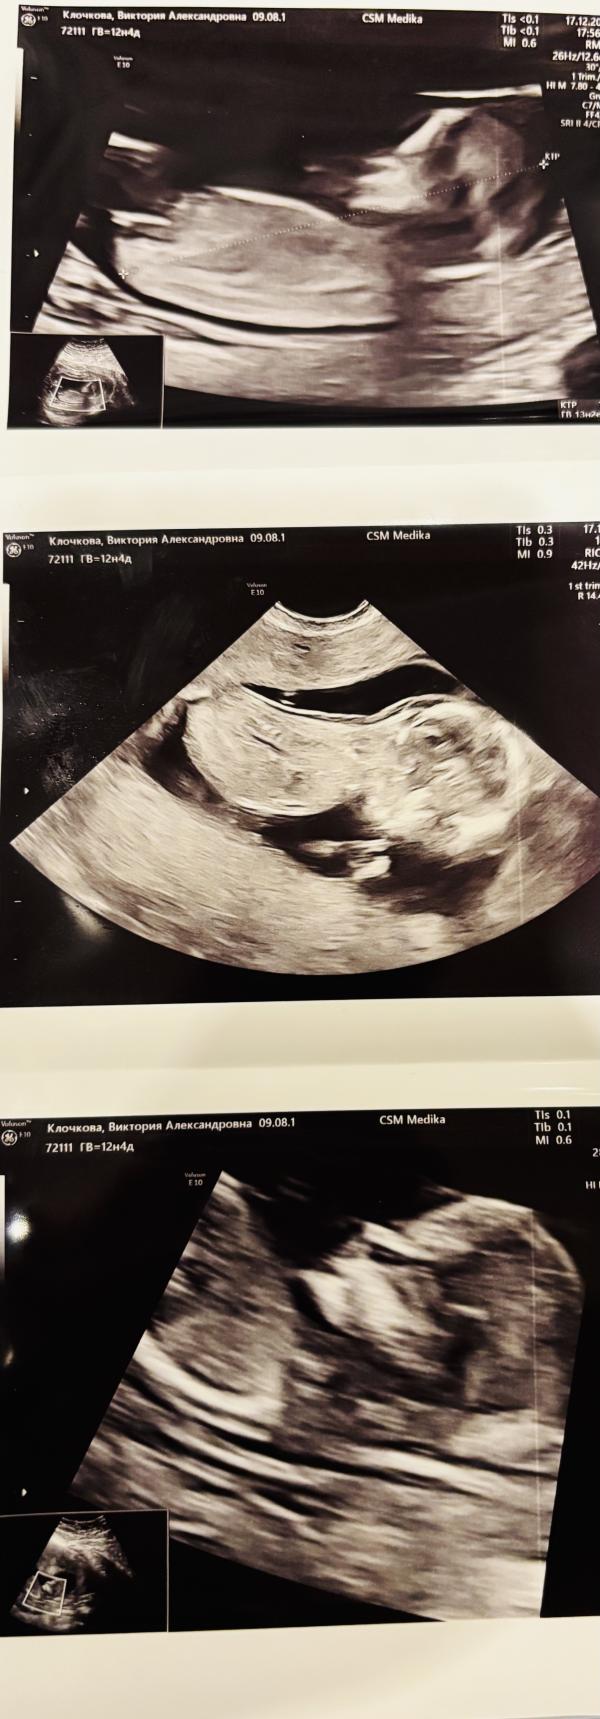

Первый скрининг пройден ✅

Были у Саурского , смотрел 1,5 часа.

Мадам не хотела поворачиваться , лежала спиной . Но врач все таки смог все увидеть 🥰

Все хорошо 👌🏼

13.1 недель

78 грамм

Ктр 7.02

Пдр 23.06.26 🩷